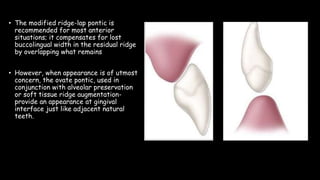

The document discusses pontic design for fixed dental prostheses. It covers pretreatment assessment of residual ridge contours, classifications of ridge deformities, surgical modification techniques, and ideal requirements for pontics. Pontic designs are classified based on their shape and materials. Factors in pontic selection include esthetics and oral hygiene. Common designs for anterior and posterior regions are described, including sanitary, ovate, and saddle pontics. Biological considerations for pontic design involve maintaining the residual ridge, abutment teeth, and supporting tissues.